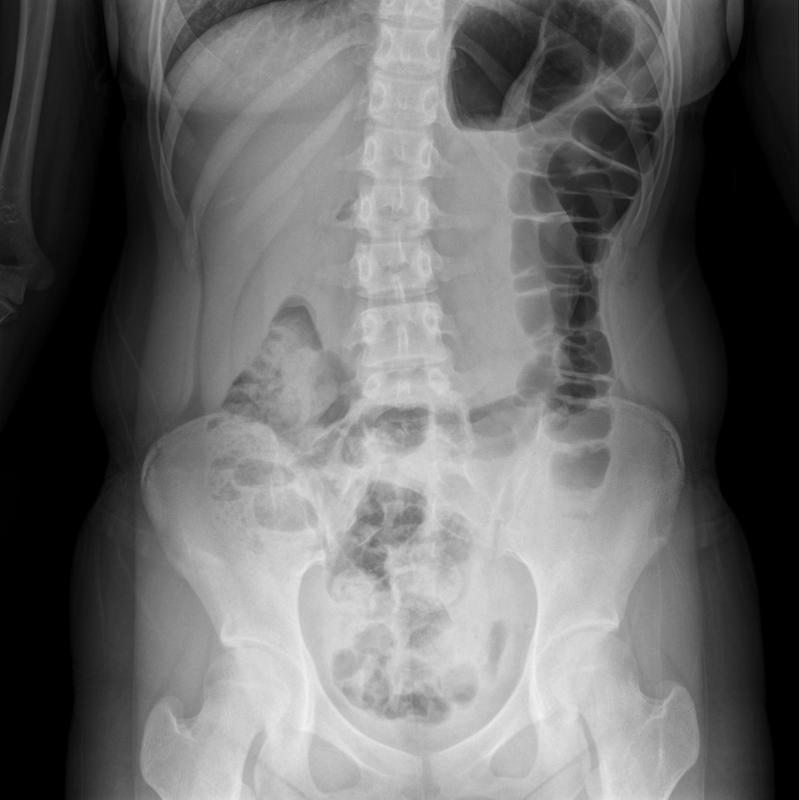

我們要了解什么是腰椎間盤突出癥?第一點(diǎn)從癥狀來(lái)說(shuō),大家首先了解到是腰椎間盤突出癥首要癥狀是腰痛,但是很少人知道還有下肢放射性疼痛(根性疼痛),椎體與椎體之間是椎間盤,椎間盤分為兩層,內(nèi)層是髓核、外側(cè)是纖維環(huán),隨著時(shí)間的推移。里層的髓核枯竭,向外,導(dǎo)致外層的纖維環(huán)破裂,兩側(cè)的神經(jīng)根受壓,為什么說(shuō)的有的患者是左側(cè)下肢疼痛(是纖維環(huán)破裂,向后突出,壓倒左側(cè)神經(jīng)根)。同理右側(cè)下肢出現(xiàn)疼痛、麻木也很好解釋!第二點(diǎn)從影像學(xué)來(lái)說(shuō),建議大家去醫(yī)院的時(shí)候,最好能夠做過(guò)腰椎的CT檢查,可以判斷腰椎間盤突出癥的輕重程度!一般我們以5mm為基準(zhǔn),5mm以上為脫出、5mm以下為膨出、5mm為突出。第三點(diǎn)從醫(yī)師的體格檢查來(lái)說(shuō),最普遍的是直腿抬高試驗(yàn),直腿抬高試驗(yàn)60°為陽(yáng)性。從這三點(diǎn),我們大致知道我們是不是腰椎間盤突癥。我們無(wú)論是采取保守治療還是手術(shù)治療,腰椎間盤突出癥的恢復(fù)期起到關(guān)鍵性的作用,為什么有的人容易復(fù)發(fā),有的人不容易復(fù)發(fā)?關(guān)鍵在于這3點(diǎn)原則有沒有做好!1、動(dòng)靜結(jié)合原則,動(dòng)是指的我們的功能鍛煉,在恢復(fù)期我們的功能鍛煉要做好,比如腰背肌功能鍛煉(五點(diǎn)支持式)靜指的是我們臥床休息,要多臥床休息為主。特別是在做完手術(shù)后,要臥床休息為主!一般要選擇硬板床,對(duì)腰部才有支撐力!2、適度原則,我們功能鍛煉要掌握適度原則,拿五點(diǎn)支撐式來(lái)說(shuō)我們一天做兩組,早上一組做10到15次下午一組做10到15次堅(jiān)持1到3個(gè)月基本有效!假如沒有掌握適度原則,超過(guò)訓(xùn)練的次數(shù),對(duì)腰椎的恢復(fù)是起到反作用!3、彎腰運(yùn)動(dòng),有彎腰的運(yùn)動(dòng)我們盡量要少做,比如騎自行車,特別是在腰椎間盤突出癥的急性發(fā)作期(2個(gè)星期以內(nèi)),騎自行車這種運(yùn)動(dòng)本身就是彎腰,然后又是蹬腿的運(yùn)動(dòng),反而是加重了病情!還有打籃球這種劇烈的運(yùn)動(dòng),本身腰痛和下肢疼痛,劇烈的運(yùn)動(dòng)反而加重了病情的發(fā)展!